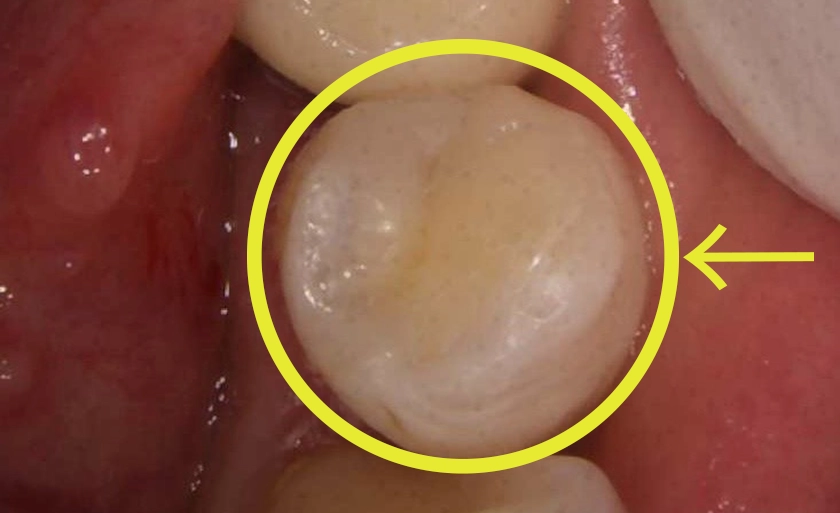

虫歯を削った歯にレジン(複合樹脂)を直接詰める治療法です。保険診療では、15〜30分の限られた時間内で、保険制度で定められた範囲内の基本的な処置のみを行うことになります。

また従来のインレー治療と違い、健康な歯まで削る必要がなく、型取りや複数回の通院も不要です。

| 審美性 | 自然な白さが長期に保てます |